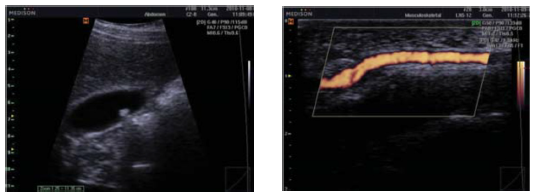

Mediante la utilización de tecnología de color excepcional 3D, su pantalla LCD de 15 pulgadas muestra imágenes claras y fácilmente visibles en hasta 640 x 450 píxeles para ayudar a aumentar la precisión diagnóstica. El SonoAce R5 provee usos múltiples en aplicaciones a las que se incluye especialidades como son: Abdominales, Vasculares, Partes Blandas, Obstetricia, Ginecología, Urología, Pediatría, etc.

El sistema proporciona alta calidad de resolución de la imagen y sensibilidad en todos los modos de exploración incluyendo los modos B/D/M/C, THI o Imagen Harmonica Tisular y 3D en modo Free hand o “Manos Libres”. El sistema admite transductores de arreglo de fase convexo, lineal y endocavitario, además es compatible con DICOM 3.0 y puede conectarse fácilmente a redes de PACS.